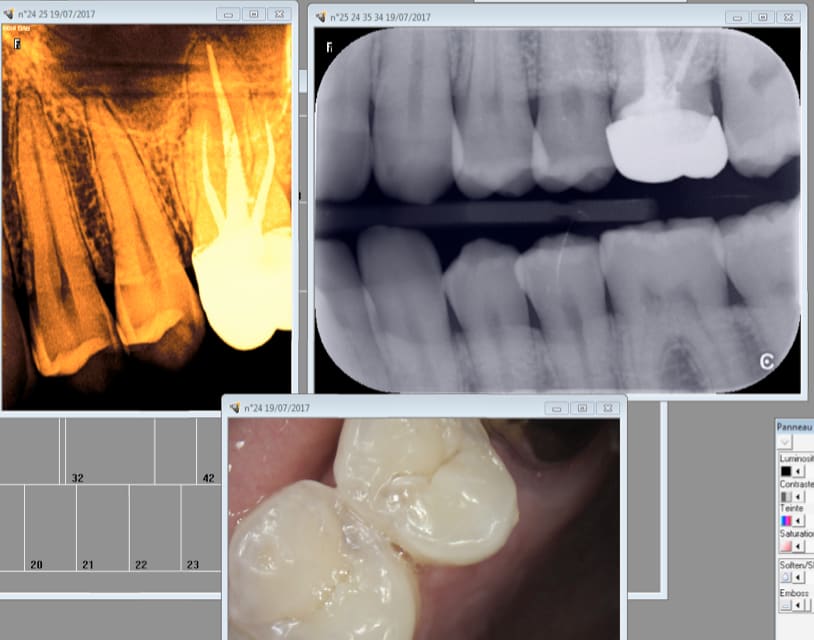

Capture d écran 2017 07 19 11.40 - Eugenol

Capture d écran 2017 07 19 11.39 - Eugenol